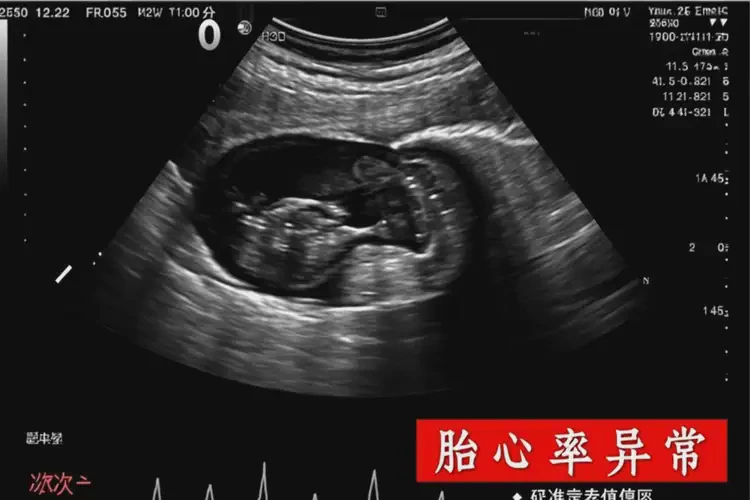

孕2周1天胎心率87還要保胎嗎(圖2)